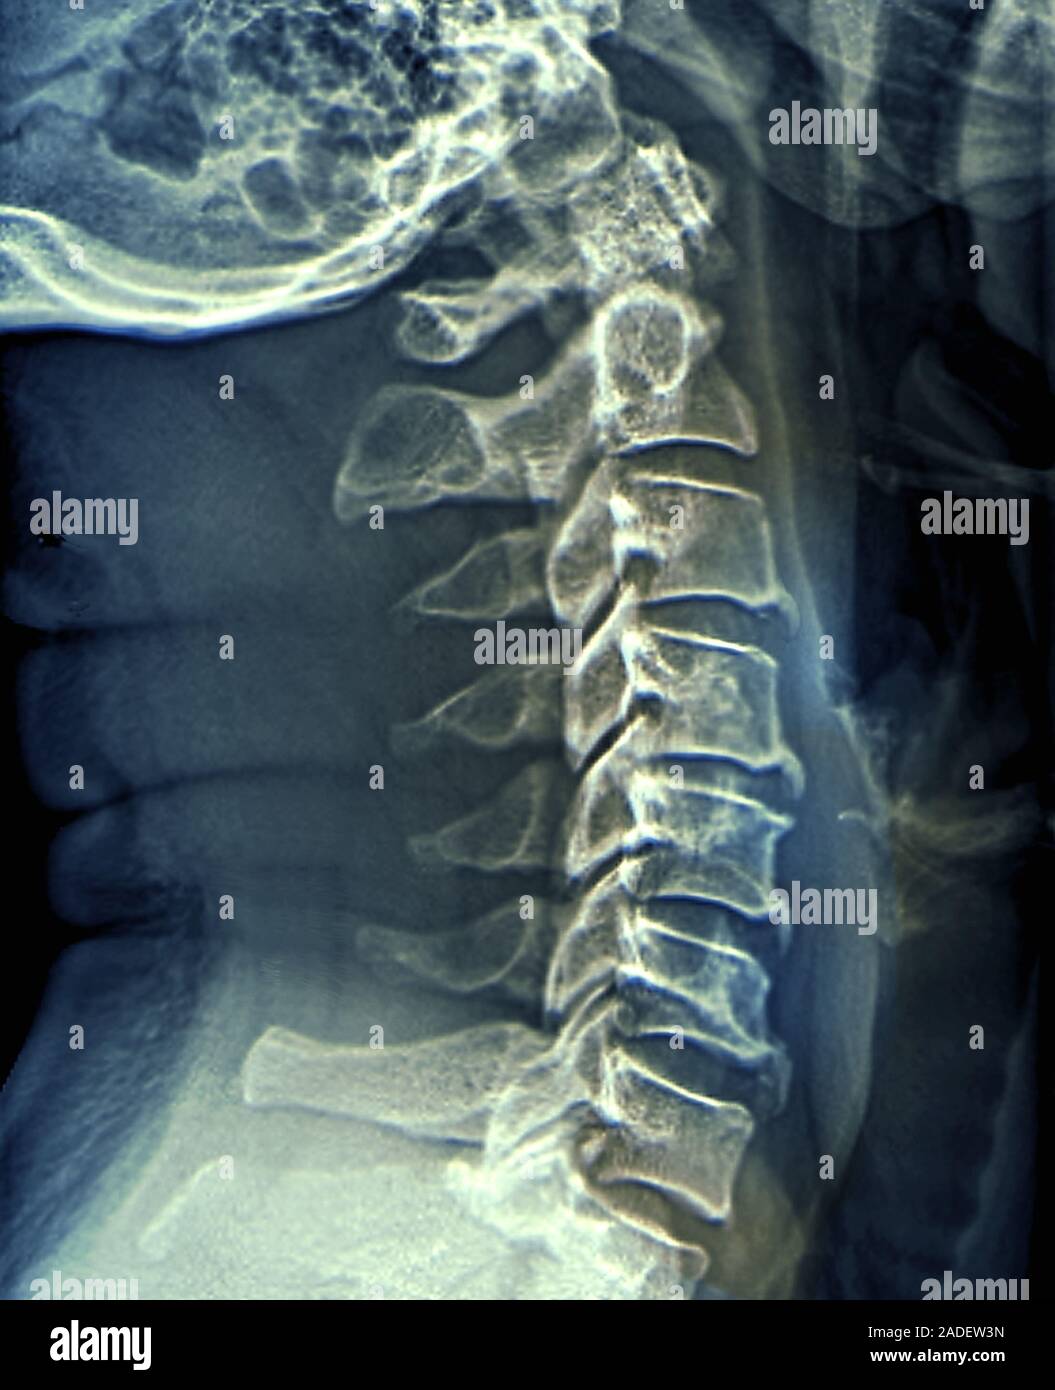

Arthritis X Ray Neck . This includes the seven bones of your neck that surround and protect the top section of. Neck arthritis can cause neck pain, stiffness, tingling, numbness, and headaches as well as neck clicking at the base of the skull. It can also reveal degenerative changes in your cervical spine. Arthritis neck pain can sometimes be severe and may lead to muscle spasms and shooting pains Cervical spondylosis is a common condition that can cause neck and shoulder pain, often in people over 40. The discs may naturally dry out and shrink over time, which can lead to bone spurs and other Neck arthritis, also called cervical spondylosis, is a common condition that occurs when the cartilage and bones in the neck gradually wear down over time, leading to joint.

Neck Arthritis Treatment, Xray Photograph by Zephyr Fine Art America Arthritis X Ray Neck Cervical spondylosis is a common condition that can cause neck and shoulder pain, often in people over 40. Neck arthritis can cause neck pain, stiffness, tingling, numbness, and headaches as well as neck clicking at the base of the skull. The discs may naturally dry out and shrink over time, which can lead to bone spurs and other Arthritis neck. Arthritis X Ray Neck.

Treatment of neck arthritis, Xray Stock Image C001/7423 Science Arthritis X Ray Neck Cervical spondylosis is a common condition that can cause neck and shoulder pain, often in people over 40. This includes the seven bones of your neck that surround and protect the top section of. Neck arthritis can cause neck pain, stiffness, tingling, numbness, and headaches as well as neck clicking at the base of the skull. It can also reveal. Arthritis X Ray Neck.